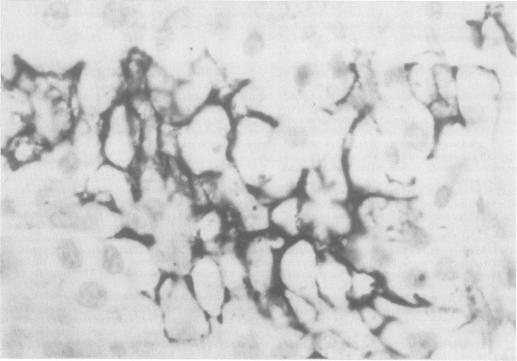

Two cases of von Hippel-Lindau's disease with special reference to the occurrence of renal carcinoma are presented. The first case demonstrates the difficulty of differentiating cerebellar haemangioblastoma from metastatic renal carcinoma affecting the cerebellum. The valuable differentiating histological features were positive staining of metastatic renal carcinoma by antiepithelial membrane antigen (anti-EMA) and the demonstration of a distinct pattern of packeting of cells by staining reticulin fibres. Staining with periodic acid Schiff and cytokeratin antibody (anti-CK) were not found to be useful. The second case exhibits the wide variety of neoplasms which may be present in von Hippel-Lindau's disease. Special stains support the findings of the first case.

本文报告两例von Hippel-Lindau病,并特别提及肾癌的发生情况。第一例显示了区分小脑血管母细胞瘤与影响小脑的转移性肾癌的困难。有价值的鉴别组织学特征是转移性肾癌对抗上皮膜抗原(抗EMA)呈阳性染色,以及通过网状纤维染色显示出明显的细胞包裹模式。未发现过碘酸希夫染色和细胞角蛋白抗体(抗CK)染色有用。第二例展示了von Hippel-Lindau病中可能出现的多种肿瘤。特殊染色支持第一例的结果。